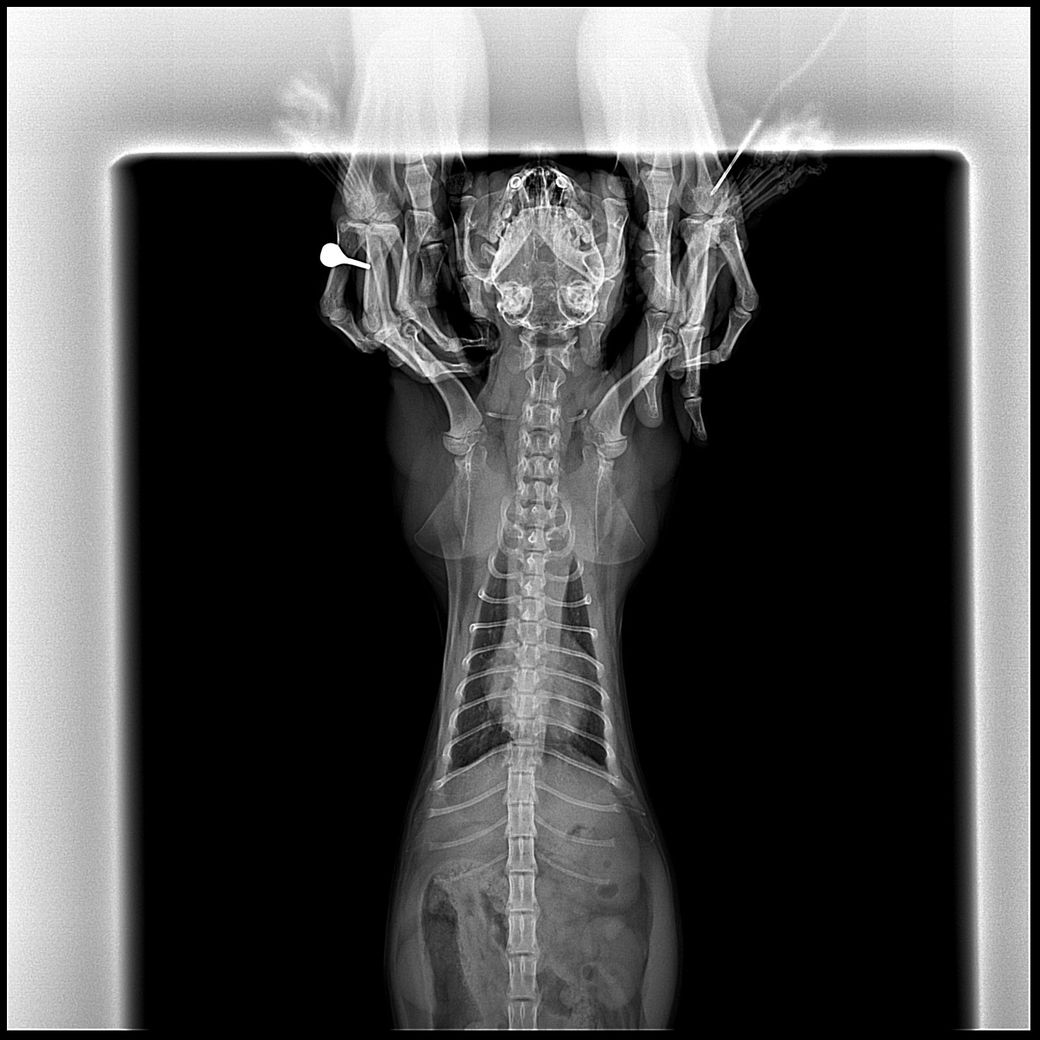

8개월된 고양이 흉부 엑스레이 촬영 후, 흉선이 작아지지 않았다는 소견을 받았습니다. 혹시 림프종이나 종격동 관련 지병일 가능성이 있을까요?

예, 종격동의 폭이 정상보다 3배 수준 이상으로 넓고, 변연이 직선형이기 때문에 종격동내 물이 차있는 상태를 의심해야 합니다. 림프종도 가능성은 있지만 환자의 연령을 고려할때 그 가능성은 낮고, 복막염이나, 식도파열, 감염성 종격동염 등의 가능성, 출혈 등을 의심해야 합니다. 주치의와 진솔한 상담 받으시기 바랍니다. 필요에 따라 CT 검사가 추천됩니다.